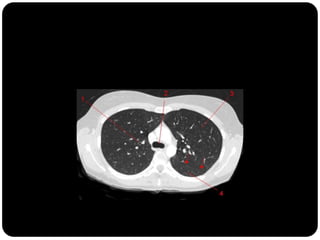

Vias aéreas

O que está anormal?

Traqueobroncopatia

osteocondroplásica

Depósito submucoso

ósseo e cartilaginoso

Depósitos nodulares ->

irregularidade

Preservação da parede

posterior membranosa da

traquéia;

Em geral placas

calcificadas;